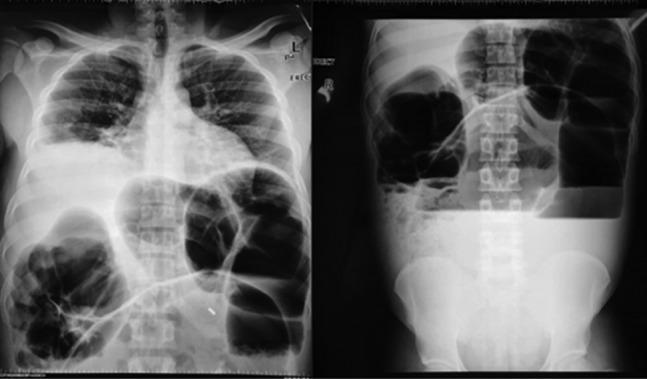

We present a 26-year-old male patient who presented with complete bowel obstruction and peritonitis. His abdominal X-rays showed grossly distended large bowels with air-fluid levels. A differential diagnosis of sigmoid volvulus was entertained and the patient was taken for an exploratory laparotomy. Intraoperatively, we found a sigmoid volvulus and a concurrent transverse colon volvulus. A subtotal colectomy and colostomy was performed. The histopathology results showed mucosal and submucosal congestion, chronic inflammation, and no malignancy or dysplasia. Synchronous volvulus of the sigmoid and transverse colon is an extremely rare. Management includes endoscopic derotation and decompression followed by semi-elective surgery in non-complicated cases. When endoscopic decompression has failed or there is suspicion of necrosis or perforation, surgery is mandatory.

我们报告一名26岁男性患者,其表现为完全性肠梗阻和腹膜炎。他的腹部X线片显示大肠明显扩张,伴有气液平面。考虑乙状结肠扭转的鉴别诊断,该患者接受了剖腹探查术。术中,我们发现乙状结肠扭转并同时存在横结肠扭转。进行了次全结肠切除术和结肠造口术。组织病理学结果显示黏膜和黏膜下充血、慢性炎症,无恶性肿瘤或发育异常。乙状结肠和横结肠同步扭转极为罕见。治疗包括内镜下复位和减压,在非复杂病例中随后进行半择期手术。当内镜减压失败或怀疑有坏死或穿孔时,手术是必需的。